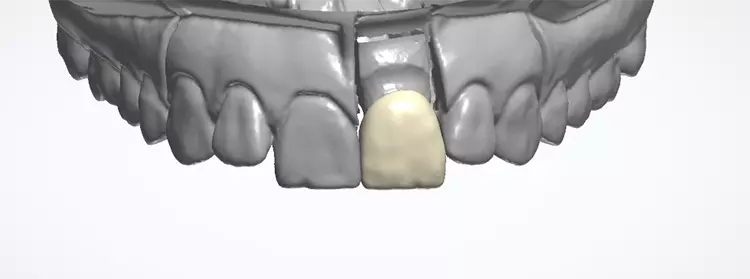

Es sollte ein Zirkonoxidmaterial mit hochästhetischen Eigenschaften zum Einsatz kommen. Die Wahl fiel auf IPS e.max ZirCAD Prime, ein Werkstoff der zwei Zirkoniumdioxid-Rohstoffe kombiniert: im Dentinbereich ein 3Y-TZP-Zirkonia mit hoher Festigkeit (1.200 MPa Biegefestigkeit) und im Schneidebereich ein transluzenteres 5Y-TZP-Zirkonia (650 MPa Biegefestigkeit). Der stufenlose Farb- und Transluzenzverlauf in den Materialscheiben ist ein zusätzlicher Vorteil für derartige Restaurationen im sichtbaren Bereich.

Das Ausarbeiten von Details und die minimale Reduktion der Labialfläche für das Microveneering erfolgt grundsätzlich im weichen, kreideartigen Weißzustand. Das so bearbeitete und modifizierte Gerüst wird nun bei 1.530 °C gesintert und schrumpft dabei volumenmäßig um ca. 25% zum eigentlichen hochfesten Zirkonoxidgerüst.

Zur Realisierung eines möglichst naturgetreuen Behandlungsergebnisses wurde labial ein minimales Cut-back und eine anschließende individuelle Schichtung mit der Verblendkeramik IPS e.max Ceram durchgeführt (Mikroveneering) (Abb. 30–33). Damit der verfärbte Zahnstumpf unter der neuen Zirkonkrone nicht mehr sichtbar ist, wird bei transluzentem Zirkoniumdioxid im Weißzustand auf der Innenseite des Gerüstes ein Opakerliquid aufgebracht. Dieses Liquid trägt nicht auf, da das Material in den Werkstoff eindringt und das Zirkongerüst an den gewünschten Stellen von innen blickdicht, sprich opak, wirken lässt (Fa. BriegelDental) (Abb. 34 und 35).